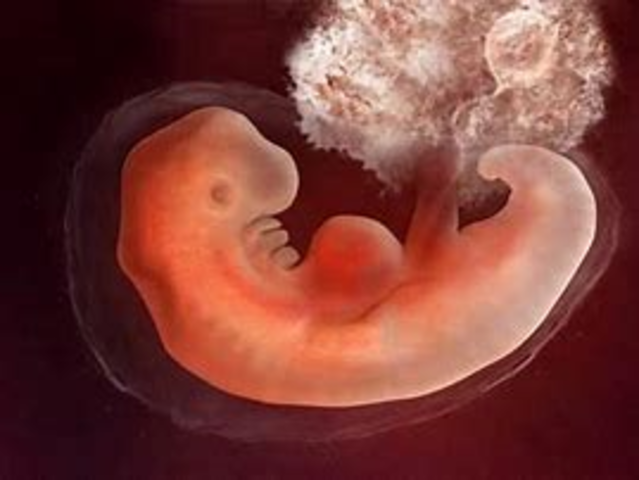

• Segundo mes 5 .a- 6 .a Semana

Segundo mes 5 .a- 6 .a Semana

Del embrión al feto. 5.a-6.a semanas Se forman los dientes. El corazón se ha hecho tan grande que forma una pequeña protuberancia; se dibujan las cuatro cavidades cardíacas. Se desarrollan el estómago, el intestino, el páncreas y el aparato urinario.

• 7.a-8.a semanas

Se individualizan los dedos de las manos y los pies, y los diversos segmentos de los miembros. Se empiezan a formar las glándulas sexuales. Paralelamente, se desarrollan los músculos y los nervios, al igual que la médula ósea. Los elementos de la cara se ven con mayor nitidez: dos pequeñas prominencias corresponden a los ojos; dos hoyuelos, a las orejas; y una pequeña abertura, a la nariz y la boca. Acaba el período embrionario, embrión mide entre 3 y 4 cm y pesa de 2 a 3 g.